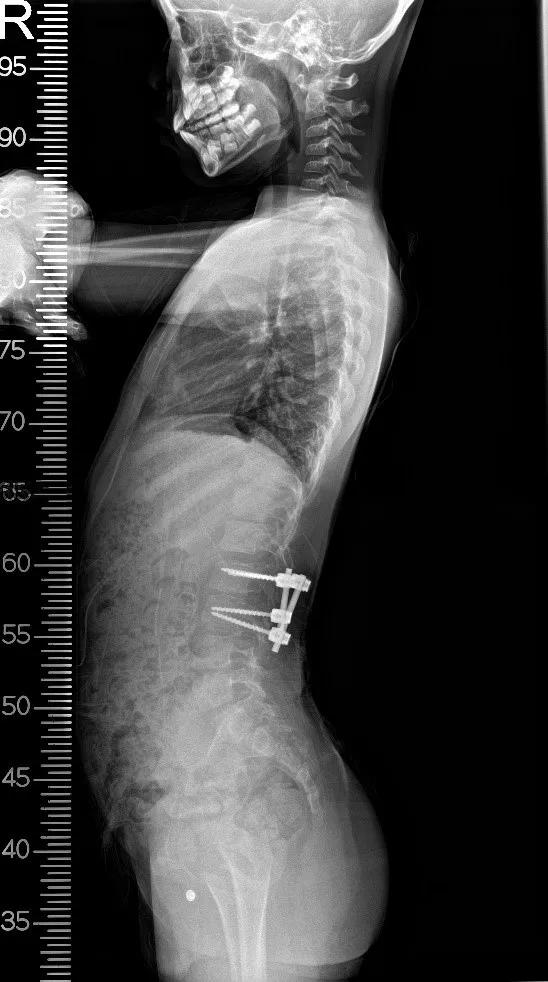

术前侧位

术后侧位